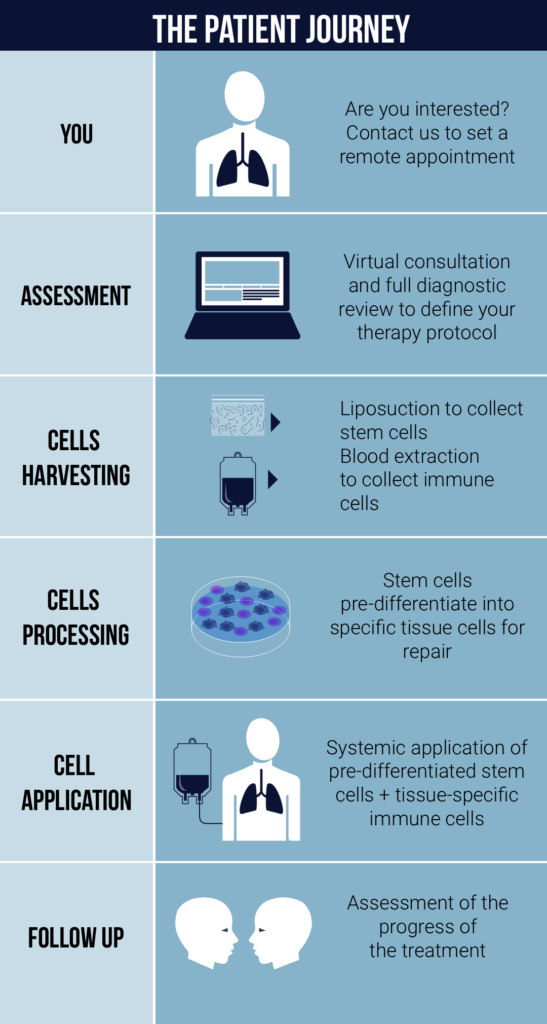

Moviglia Method therapy is a simple and effective procedure completed in a single outpatient visit. Here’s a step-by-step guide to what patients can expect:

EVALUATION PRE-TREATMENT

Clinical evaluation is complemented with Pulmonary function tests (Spirometry, lung diffusion, oximetry) and imaging (Chest X ray and CT scan).

HARVESTING

Two types of cells are needed for the treatment: stem cells and tissue-specific effector lymphocytes. The stem cells are extracted from subcutaneous fat, which is done by performing a micro liposuction procedure that only needs local anesthesia. Immune cells are obtained from the patient’s peripheral blood.

CELL PROCESSING

The collected fat is processed to isolate and expand the stem cells. The combination of the stem cells and the tissue specific effector lymphocytes facilitates the pre differentiation of the stem cells into the specific cells that the tissue needs to repair the damage (lung and vascular structures).

CELL APPLICATION

Pre-differentiated cells, together with tissue-specific lymphocytes, are given by intravenous infusion. The infusion is repeated every 4 to 8 weeks for one year. Lung function tests are performed every 6 months.